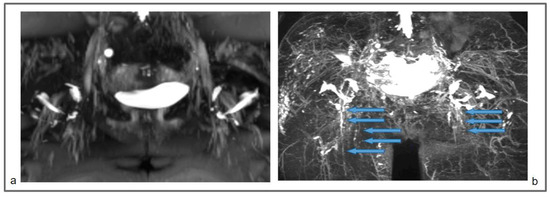

For a comparison (Figure 10), we also show the preoperative MR lymphography and 1-year follow-up of a 25-year-old woman affected by a right primary LE, treated with venolymphatic anastomosis. The follow-up imaging showed a decrease in the edema, but no new lymphatic vessels were recognizable.

Figure 10.

Preoperative non-contrast MR lymphography (based on high-resolution heavily T2-weighted coronal sequences (turbo spin echo with repetition time 2870 ms, echo time 797 ms, field of view 380 × 380 mm, matrix 358 × 384, slice thickness 1 mm) (a) and follow-up non-contrast MR lymphography (b) 1-year post-venolymphatic-anastomosis. Marked edema involving the lower third of the leg, the ankle, and the dorsum of the foot (blue arrows) is visible in (a), while follow-up imaging (b) shows a reduction of the edema (blue arrows), but without evidence of any new lymphatic vessels.